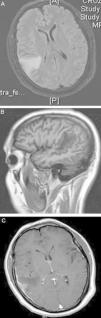

La paquimeningitis hipertrófica crónica (PHC) es un proceso inflamatorio de etiología desconocida que se caracteriza por afectar a la duramadre, provocando un crecimiento pseudotumoral de la misma. La clínica de presentación es consecuencia del efecto compresivo sobre estructuras neurológicas aunque en ocasiones se manifiesta por síntomas irritativos. El diagnóstico se realiza por exclusión de causas infecciosas, neoplásicas y autoinmunes fundamentalmente. El tratamiento esteroideo se considera la terapia más utilizada hoy en día. Se presentan 2 casos clínicos de PHC en los que se practicó resección quirúrgica de la lesión sin precisar posteriormente tratamiento coadyuvante dada la favorable evolución clínica y radiológica.

Chronic hypertrophic pachymeningitis is an inflammatory process of unknown aetiology characterised by a thickening of the dura mater causing pseudotumoural growth. Clinical manifestations are usually secondary to compression of adjacent neurological structures but may be also secondary to inflammatory processes. Diagnosis is mainly obtained by excluding infectious, neoplastic and autoimmune causes. Nowadays, steroid treatment is the most commonly used therapy. Two clinical cases of hypertrophic pachymeningitis are presented which were treated by surgery without any additional treatment and with good clinical and radiological development.